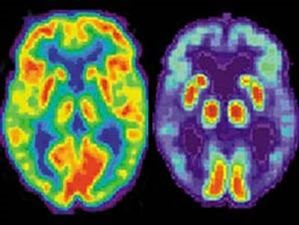

Νέες δυνατότητες για τη φαρμακευτική έρευνα της νόσου Αλτσχάιμερ ανοίγει το γεγονός ότι για πρώτη φορά νευροεπιστήμονες στις ΗΠΑ πέτυχαν να αναπαράγουν στο εργαστήριό τους καλλιέργειες ανθρωπίνων εγκεφαλικών κυττάρων, οι οποίες αναπτύσσουν όλα τα διαδοχικά βήματα της νόσου.

Η «αχίλλειος πτέρνα» της νόσου Αλτσχάιμερ μέχρι σήμερα είναι ότι δεν μπορεί να μελετηθεί σε πραγματικό χρόνο στους ανθρώπους (παρά μόνο σε νεκρούς πλέον εγκεφάλους). Το καλύτερο που είχαν πετύχει έως τώρα οι επιστήμονες, ήταν να μελετούν τη νόσο σε ποντίκια που είχαν μια παρεμφερή εγκεφαλική πάθηση.

Τώρα όμως, οι ερευνητές θα έχουν στη διάθεσή τους ένα πρωτοποριακό σύστημα κυτταρικής καλλιέργειας (το λεγόμενο «Αλτσχάιμερ σε τρυβλίο»), πράγμα που θα επιτρέψει μεγάλη εξοικονόμηση χρόνου και χρημάτων για την ανάπτυξη νέων φαρμάκων. Επιπλέον, η νέα μελέτη στα εργαστηριακά κύτταρα επιβεβαίωσε την κυρίαρχη υπόθεση (από τη δεκαετία του ’80) ότι το πρώτο και βασικό βήμα για την εξελικτική πορεία της ανίατης νευροεκφυλιστικής νόσου είναι η εναπόθεση της πρωτεΐνης βήτα - αμυλοειδούς στον εγκέφαλο.

Οι επιστήμονες ανέφεραν ότι, όπως διαπίστωσαν από την καλλιέργεια των εγκεφαλικών κυττάρων, όντως η εναπόθεση του βήτα - αμυλοειδούς είναι αρκετή για να ″πυροδοτήσει″ τη δημιουργία καταστροφικών πλακών, τον θάνατο των νευρώνων και τη διάχυτη εγκεφαλική φλεγμονή, έναν φαύλο κύκλο με κατάληξη τον μαζικό θάνατο των κυττάρων του εγκεφάλου.